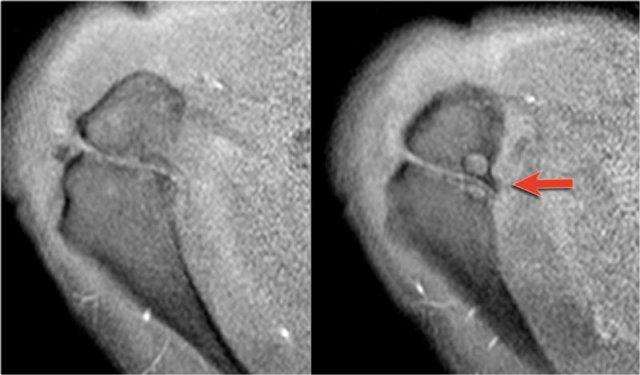

Os Acromiale

Failure of one of the acromial ossification centers to fuse will result in an os acromiale.

It is present in 5% of the population.

Usually it is an incidental finding and regarded as a normal variant.

The os acromiale may cause impingement because if it is unstable, it may be pulled inferiorly during abduction by the deltoid, which attaches here.

On MR an os acromiale is best seen on the superior axial images.

An os acromiale must be mentioned in the report, because in patients who are considered for subacromial decompression, the removal of the acromion distal to the synchondrosis may further destabilize the synchondrosis and allow for even greater mobility of the os acromiale after surgery and worsening of the impingement (4).

The axial MR-images show an os acromiale with degenerative changes, i.e. subchondral cysts and osteophytes (arrow).